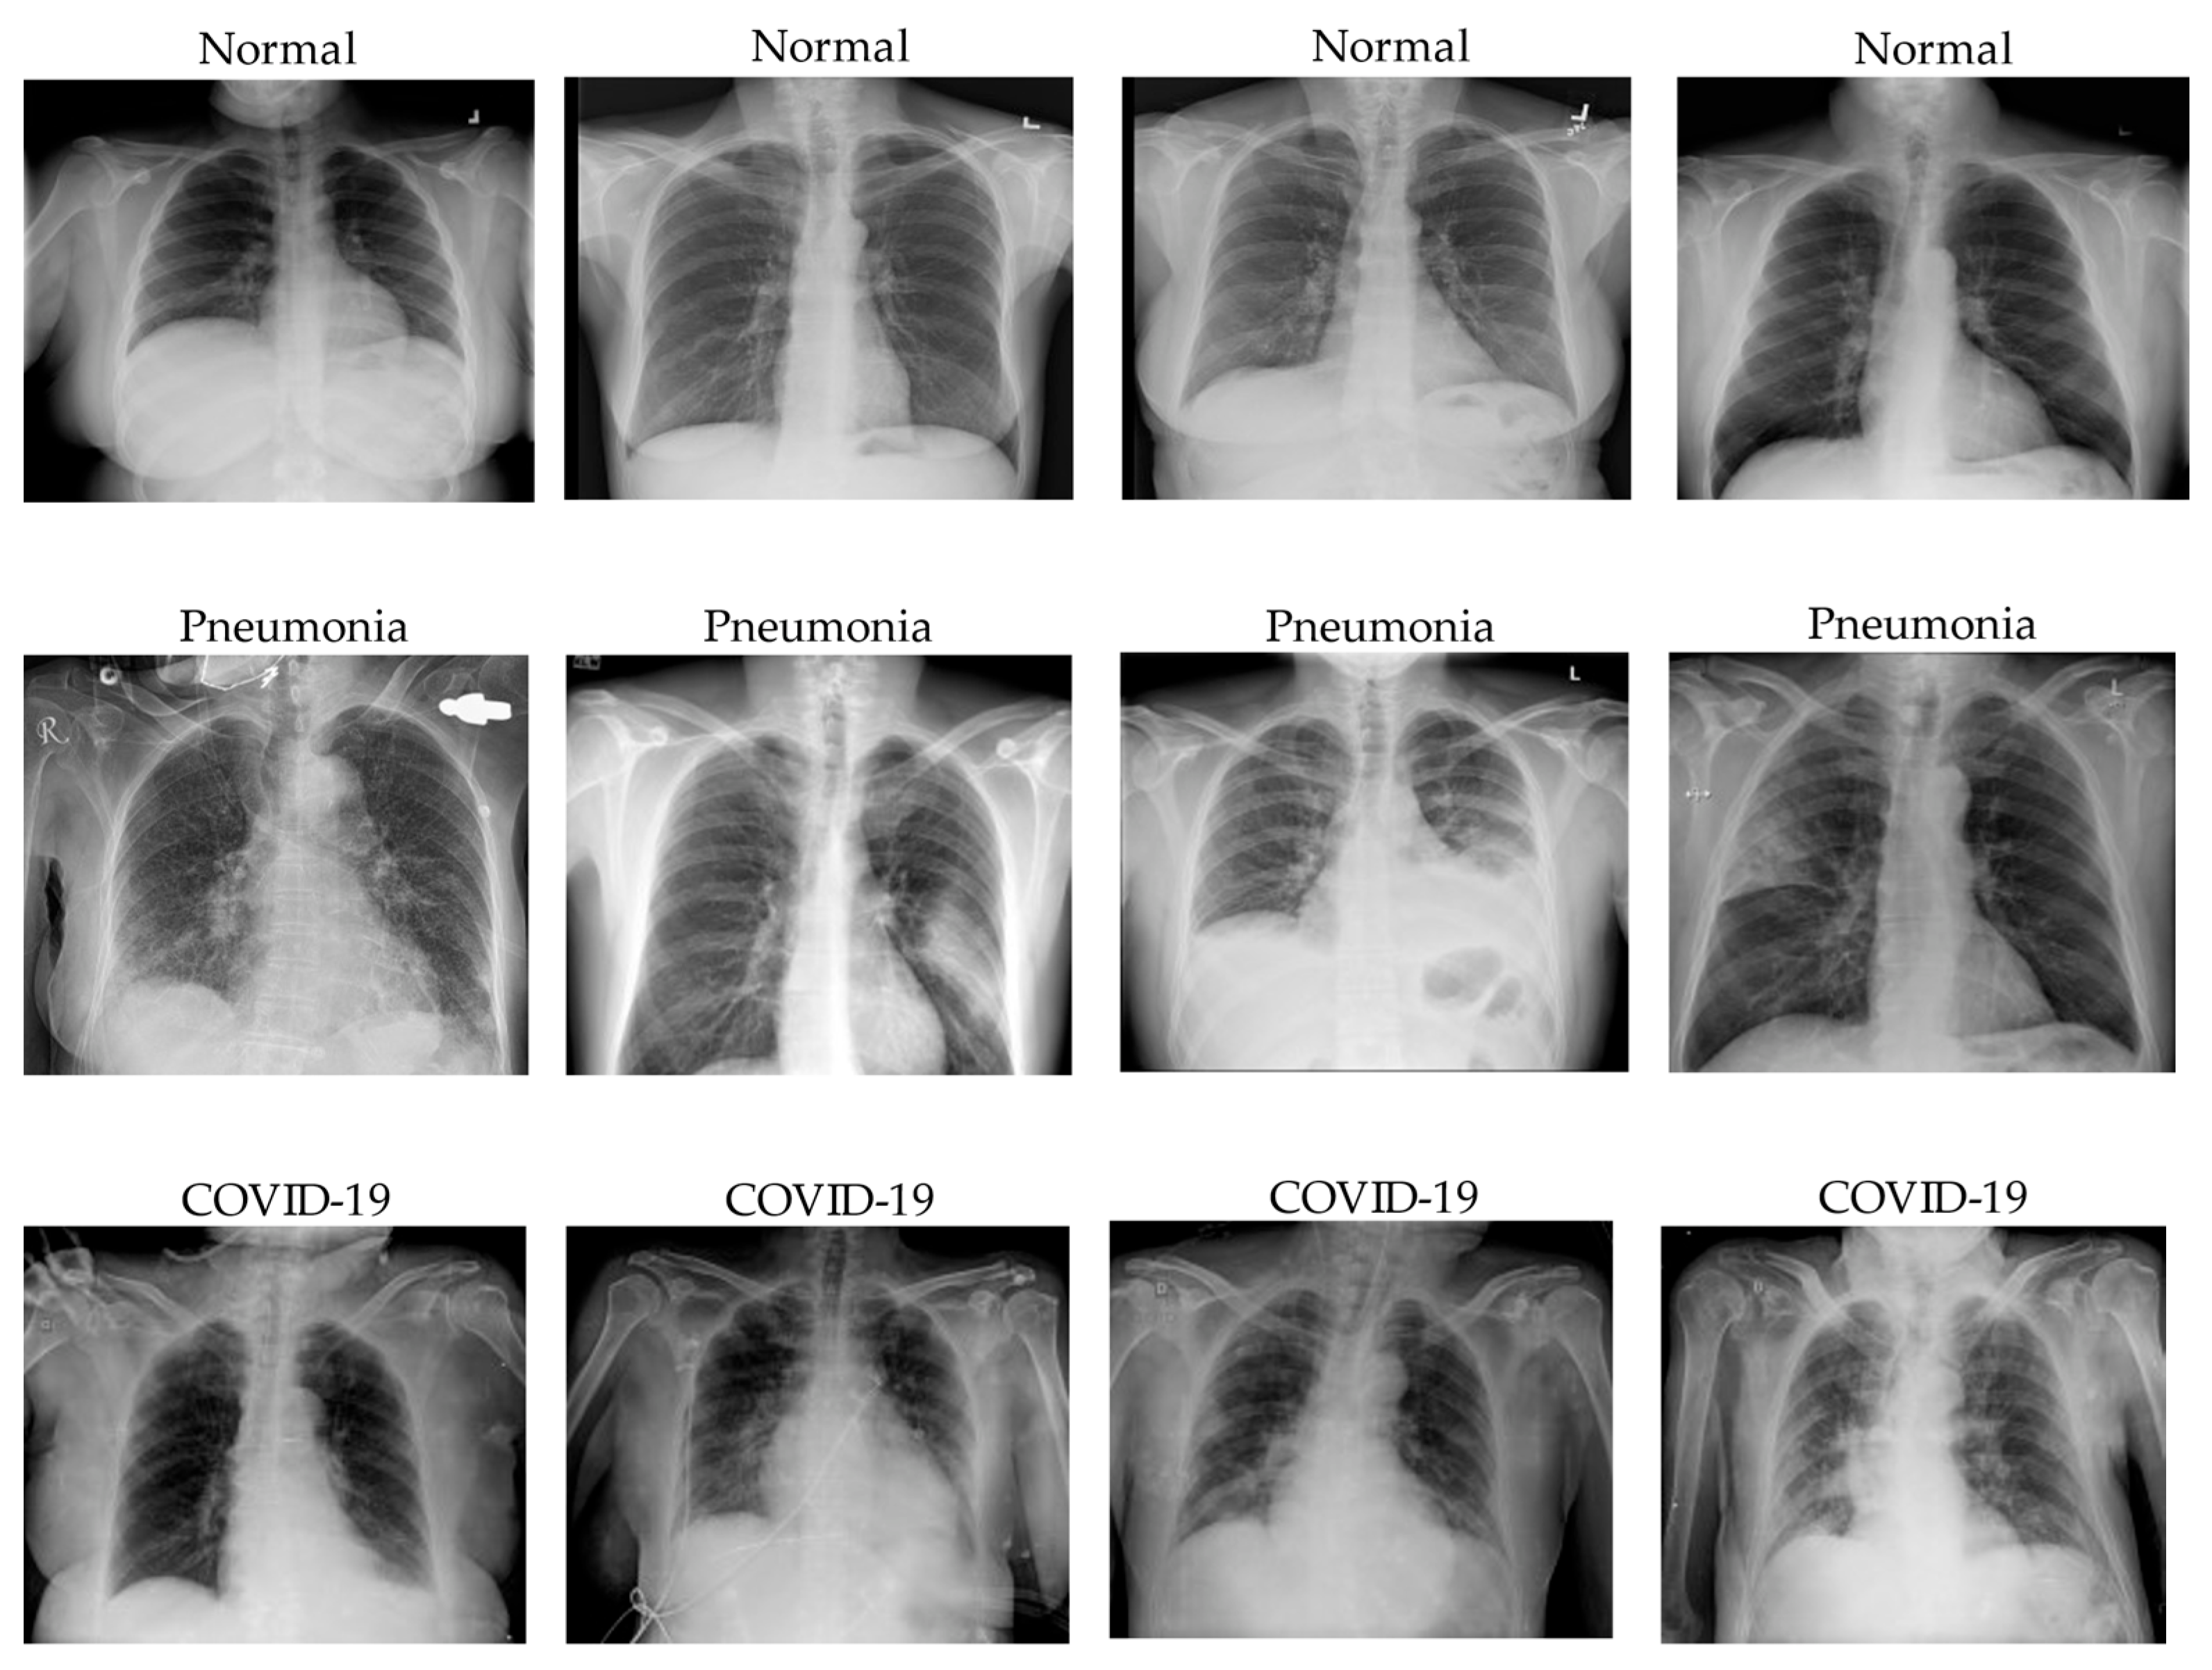

The RALO (Radiographic Assessment of Lung Opacity Score) dataset was captured and scored by Stony Brook Medicine to aid researchers with a standard COVID-19 dataset. The dataset contains 2373 chest X-ray images and was scored by two expert radiologists for further COVID-19 severity analysis. In the RALO dataset, we only separated the dataset into train and validation with 1899 and 474 images, respectively. There are 845 and 1054 images with respect to level1 and level2 in the training set. For the validation set, there are 211 and 263 images as level1 and level2. We present an illustration of level1 and level2 severity chest X-ray images in Figure 2 below.

Figure 2. Image samples from the customized COVID-19 severity assessment dataset with respect to level1 and level2 classes.